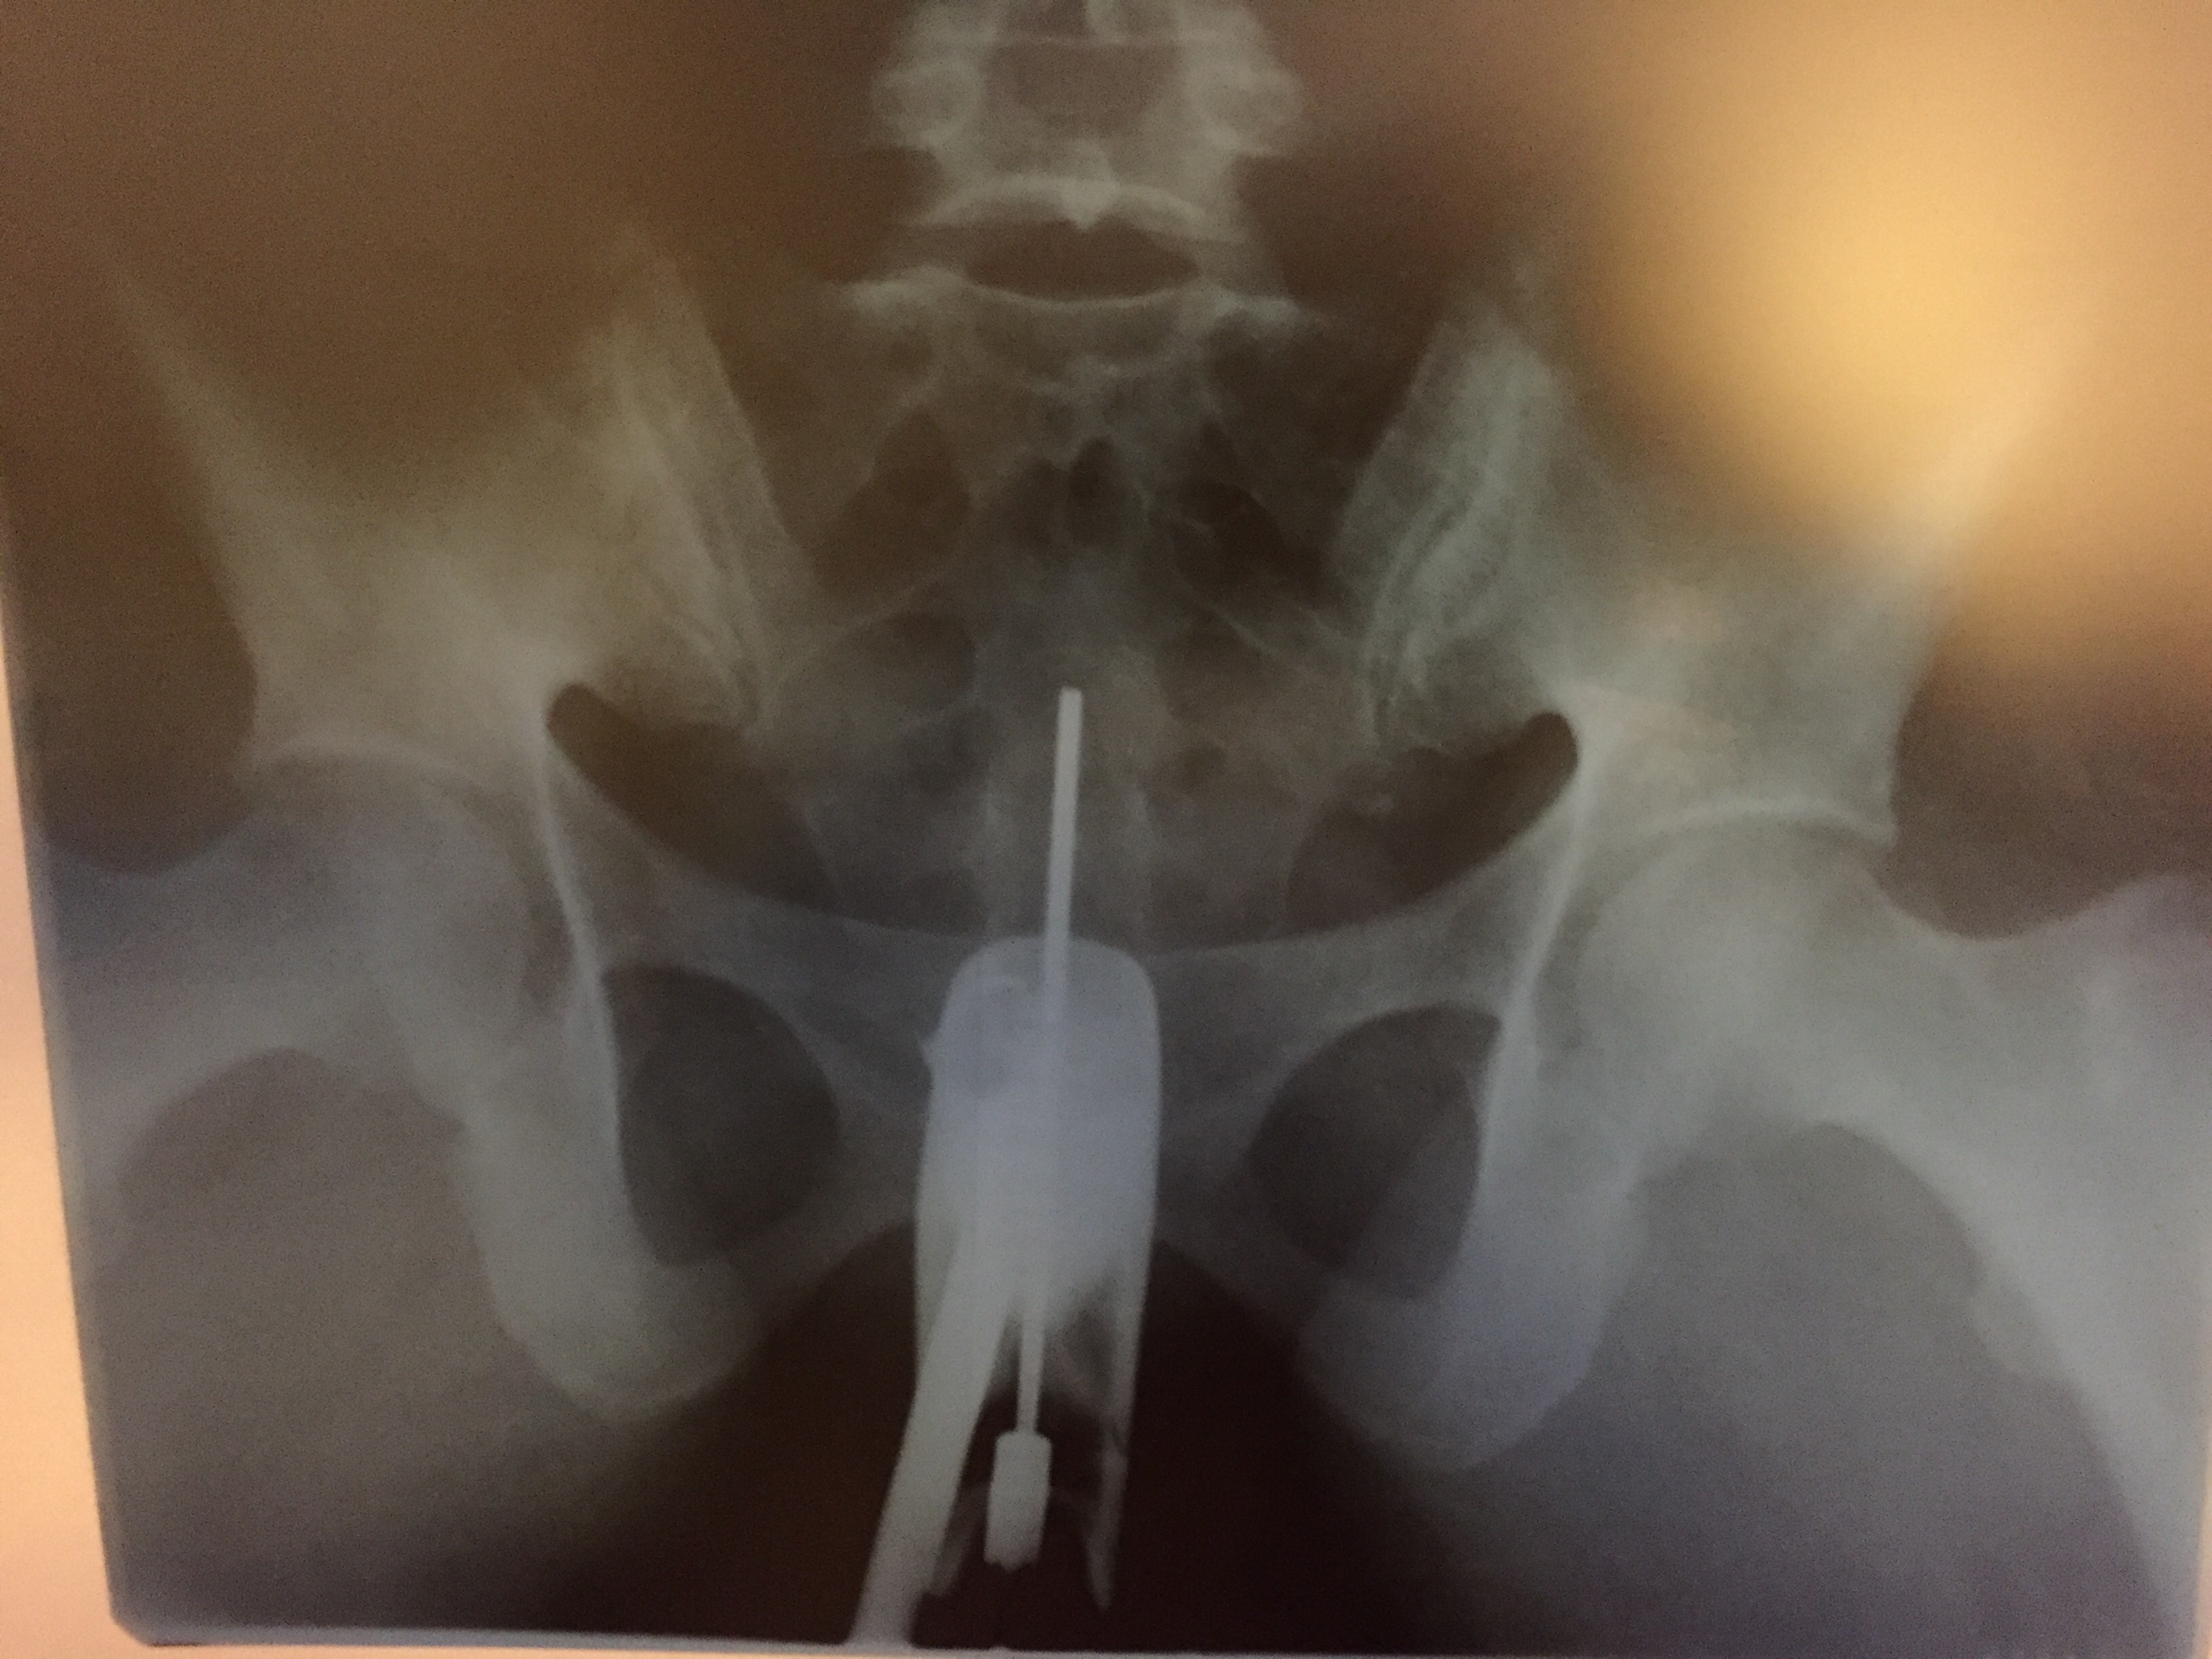

Медицинские снимки: Проходимость маточных труб